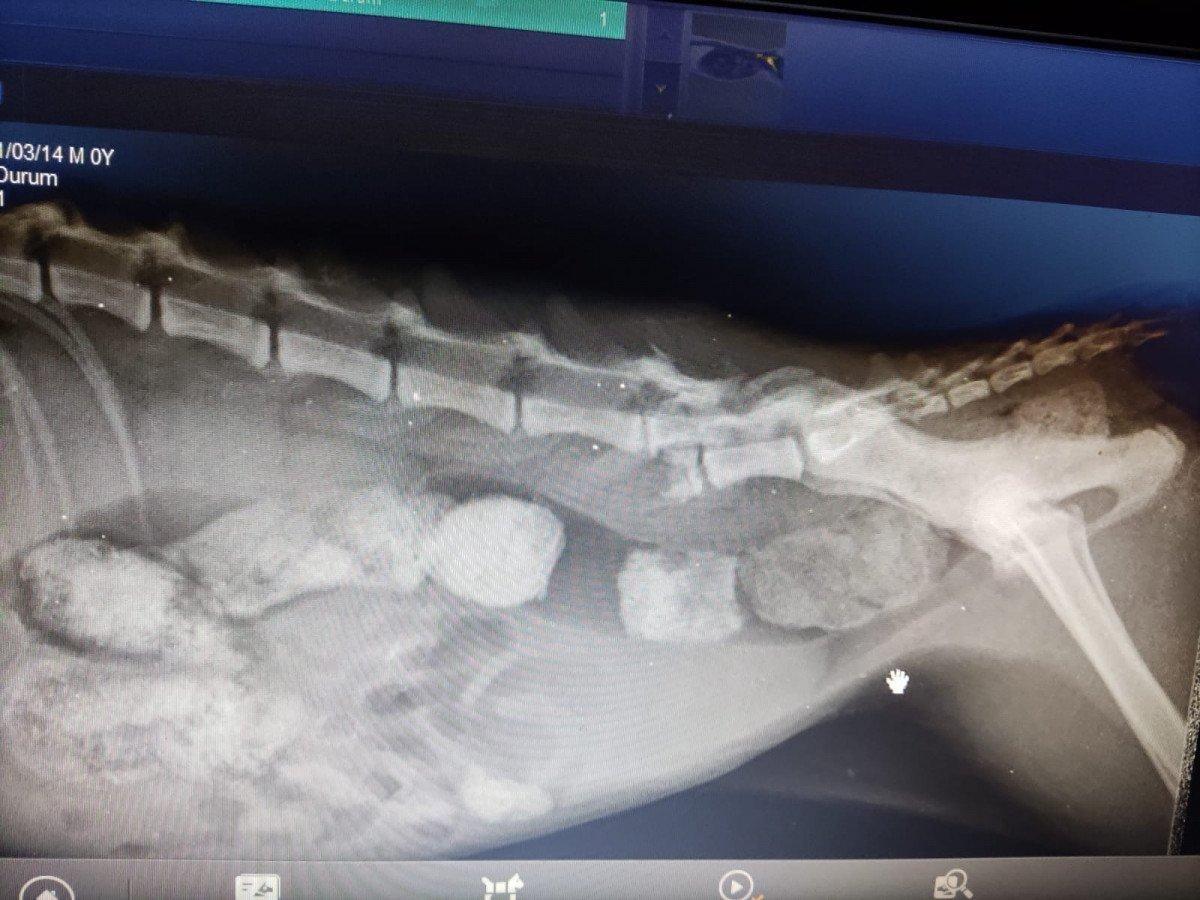

Yapılan muayenede, kedinin omuriliğinde ve arka sağ ayağında kırık olduğu tespit edildi. Ayrıca kedinin rektumunda ve bağırsaklarında 5 santimlik genişleme olduğu belirlendi.

Kedinin hayati tehlikesinin olduğunu ifade eden Yazıcı, "İlk etaptaki muayenesinde rektum bölgesindeki 4-5 santimetrelik açıklık dikkatimizi çekti. Daha sonrasında yaz mevsiminde olduğumuz için kurtlanma durumu vardı. İlk muayenede kurtlar temizlendi. Rektum boşaltıldı. Daha sonrasında röntgen çektiğimizde omurga kırığı ve bacakta kırık olduğunu tespit ettik. Rektumdaki bu kadar büyük bir açıklık maalesef ne trafik kazası ne şiddetten kaynaklı olmayıp direkt olarak cinsel saldırı vakası olduğunu belirttik. İlk muayeneler bu şekilde." dedi.